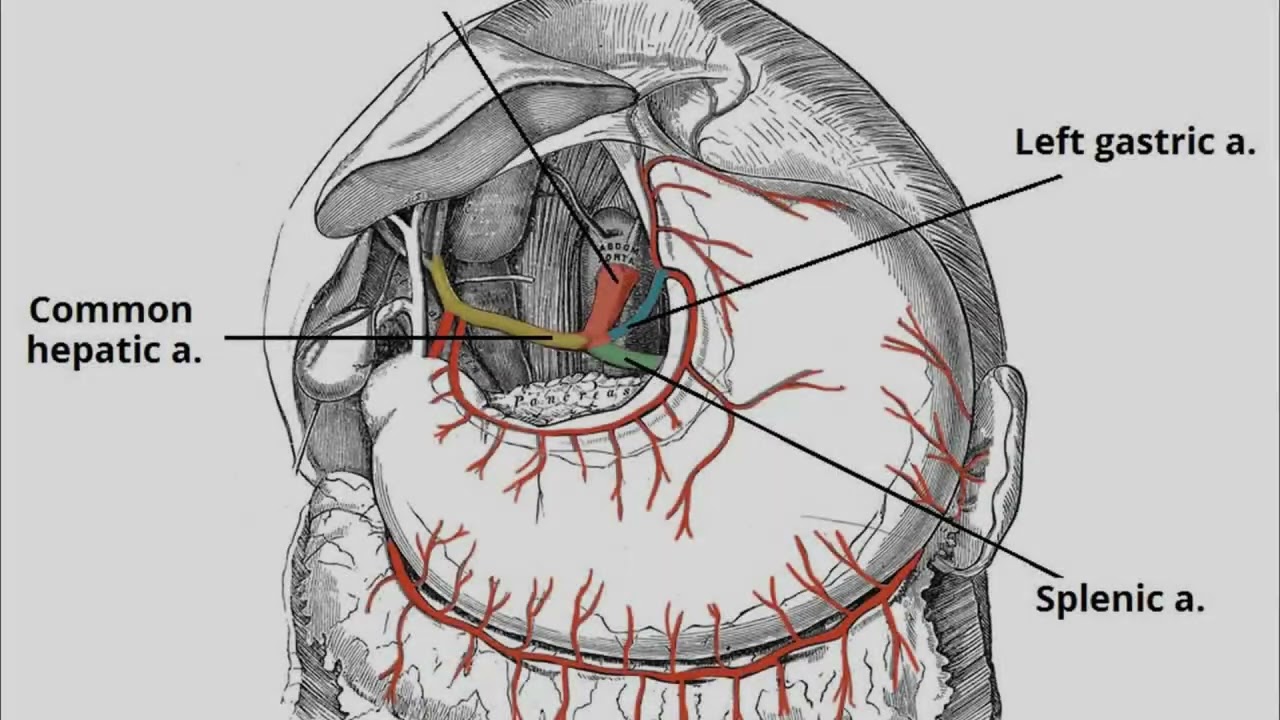

Surgical Scene Segmentation